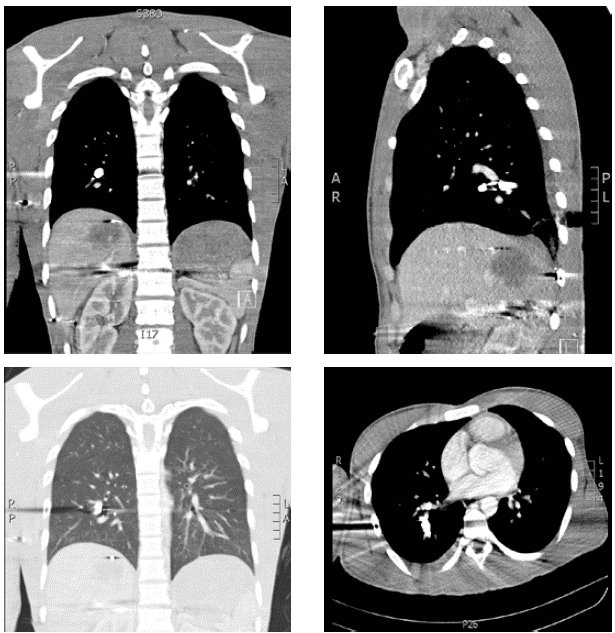

Se practicó una tomografía toracoabdominal con contraste que mostró neumomediastino: proyectil en la arteria pulmonar del lóbulo inferior derecho, con signos de embolia pulmonar aguda en sus ramas distales, proyectil en los tejidos blandos de la pared torácica posterior derecha asociado con laceración y contusión en la base pulmonar; no había neumotórax ni hemotórax; además, se apreció una laceración hepática profunda con compromiso del segmento VII, con signos de sangrado activo y hematoma subcap-sular hepático contenido (figura 1). Se ordenó una arteriografía que no demostró sangrado activo; también, se practicó angiotomografía y arteriografía del miembro superior derecho y no se encontró sangrado ni lesión vascular.

Figura 1 Angiotomografía con énfasis en el pulmón: proyectil de arma de fuego localizado en la arteria pulmonar del lóbulo inferior derecho, embolia pulmonar aguda en ramas para el lóbulo inferior derecho distal al proyectil, y proyectil en los tejidos blandos de la pared torácica posterior derecha, asociado con laceración y contusión pulmonar basal